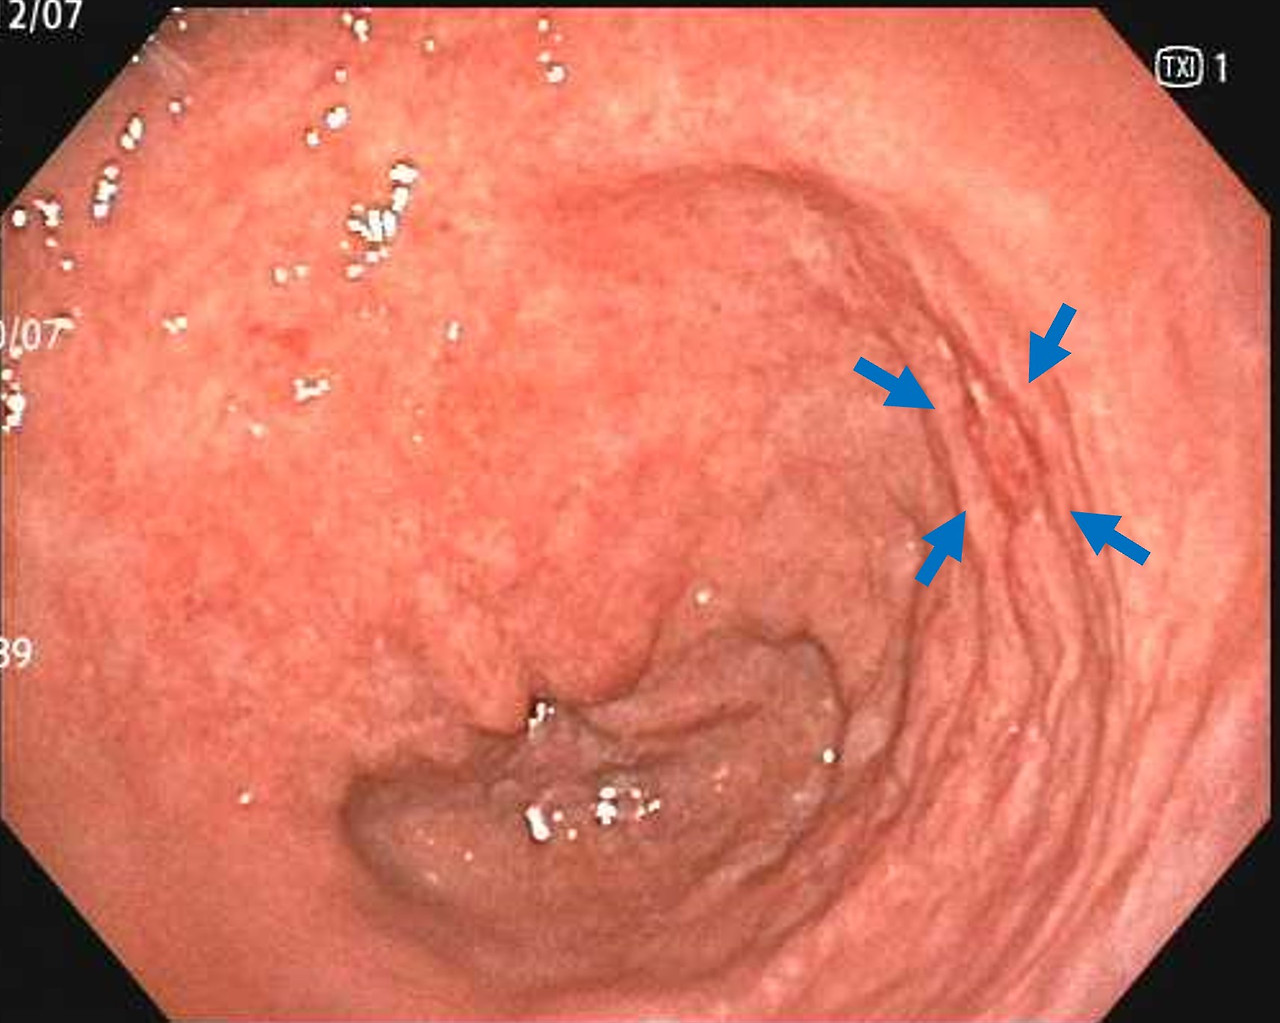

- 표면이 거칠거나 미세한 융기, 함몰이 발견되는 경우

- 장상피화생이 의심되는 구조 변화가 있는 경우

위축성 위염 및 장상피화생 평가

- 위점막의 얇아짐, 창백함

- 장점막 형태가 나타나는 변화